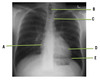

The picture shows arterial supply of the upper limbs, what is A?

Radial artery

The picture shows arterial supply of the upper limbs, what is B?

Brachial artery

The picture shows arterial supply of the upper limbs, what is C?

Subclavian artery

The picture shows arterial supply of the upper limbs, what is D?

Ulnar artery

The picture shows arterial supply of the upper limbs, what is

Axillary artery

At what bony point does the subclavian artery become the axillary artery?

Lateral border of 1st rib

In which area of the upper limb does the brachial artery branch into radial and ulnar artery?

Antecubital fossa

Of the radial and ulnar arteries, which is more superficial of the two?

What is the complete branching of the subclavian artery?

Subclavian - axillary - brachial - radial and ulnar